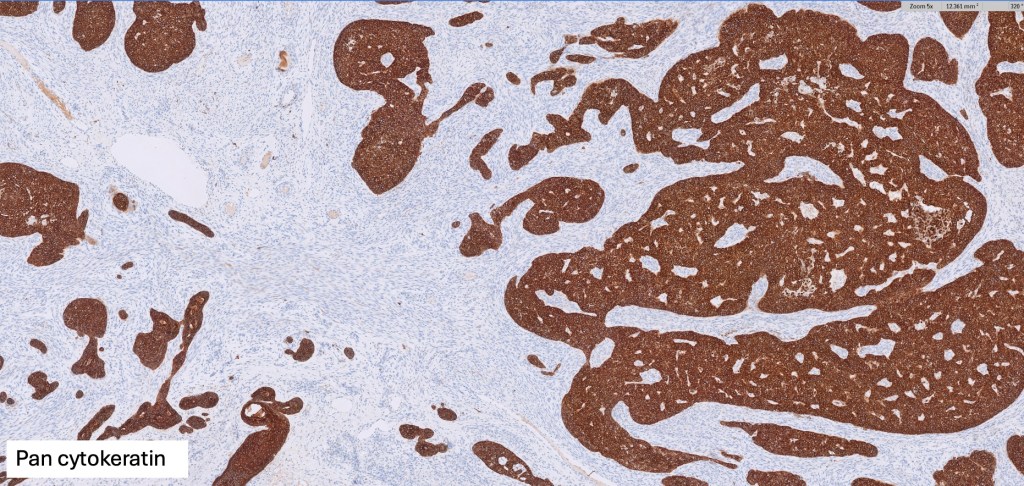

Histological features

•Low grade trichoblastic carcinoma is easily recognized as trichoblastomatous but shows an infiltrating margin with deep involvement into subcutaneous fat +/- muscle

•High grade trichoblastic carcinoma is characterized by high grade carcinoma arising in a trichoblastoma. TP53 &PIK3CA mutations have been documented